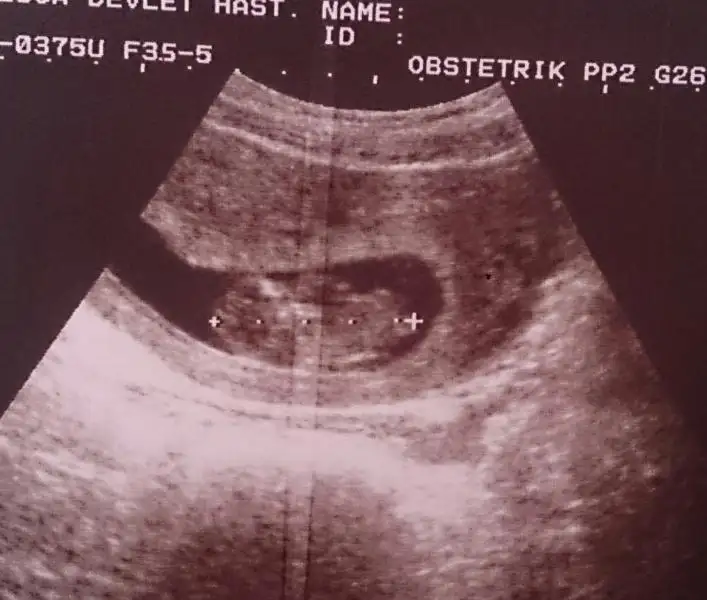

resim 1

Eki Görüntüle 473828 gordugunuz gibi ust taraftaki simgedende anlasildigi gibi eger cikinti paralel ise kiz

yok 30°lik bir aciyla yukari dogru bakiyorsa %99 oglunuz olacak demektir simdi bi kac ornek resimler daha koyacagim kiziminkide dahil